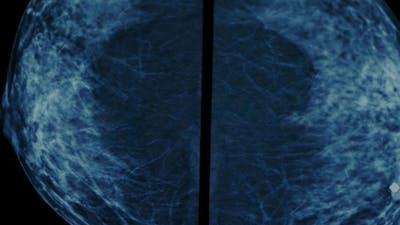

Breast cancer kills. But are blanket programs that screen all women, rather than those with symptoms, doing more harm than good? Controversially, studies into the effects of these programs show they do not reduce the risk of dying from breast cancer. Healthy women are receiving unnecessary diagnoses of pre-cancerous conditions that are unlikely to develop and many are harmed by unnecessary treatment. We follow four women from around the world who are facing the fear of cancer.